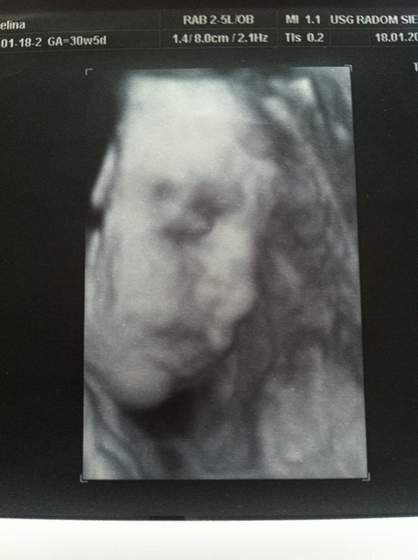

Zaraz mam przed oczami filmy z "alienami" w roli głównej. Nie mniej fajne jest to, że dzięki nim można tak dokładnie zbadać dzieciątko.